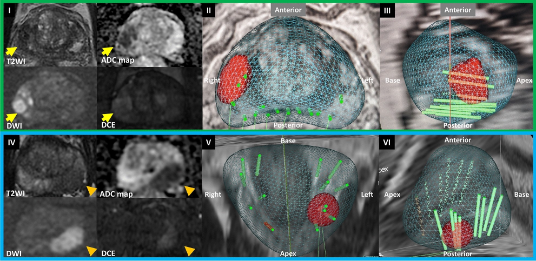

На сегодняшний день одним из наиболее информативных методов диагностики рака простаты является мультипараметрическое МРТ простаты. Аббревиатура современной классификации подозрительных участков простаты на МРТ называется PIRADS. В своем заключении МРТ простаты вы можете увидеть такое обозначение с последующим цифровым индексом от 2 до 5. Существует прямая корреляция между этой классификацией и риском рака простаты: у пациентов с PIRADS 2 вероятность рака простаты не превышает 4%, при PIRADS 3 — 13-21%, при PIRADS 4 — 38-55%, при PIRADS 5 — 73-78%. Современные протоколы диагностики рака простаты рекомендуют выполнение биопсии простаты при PIRADS 3, 4 и 5.

Технологическое развитие медицинского оборудования привело к возможности совмещения снимков МРТ и УЗИ; такая технология получила название «фьюжн». Это позволяет, при наложении друг на друга и синхронизации МРТ-изображения и ультразвукового изображения, произвести точечный забор материала из подозрительного фокуса, диагностированного на МРТ. Информативность такого исследования значительно превосходит информативность стандартной методики и снижает вероятность получения ложноотрицательных результатов.

Кроме точного выявления опухоли, фьюжн-биопсия простаты позволяет выявить тот самый агрессивный, клинически значимый рак простаты (Глисон 7 и более), что повлияет на выбор единственно правильной тактики лечения.